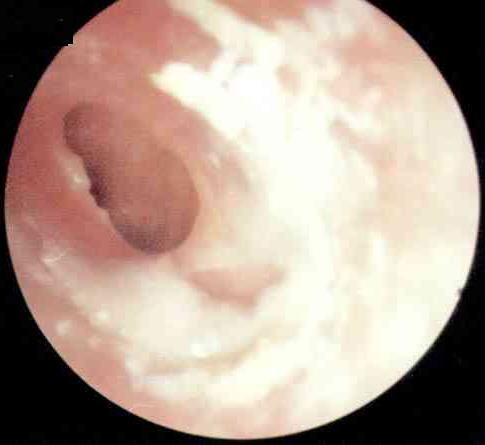

什么是胆脂瘤型中耳炎?

慢性化脓性中耳炎分为三型,有单纯型、骨疡型、胆脂瘤型。胆脂瘤性中耳炎属于型,也是这三种中耳炎中为严重,且易造成并发症的一型。所谓胆脂瘤,就是中耳里脱落的上皮的堆集,越聚越大,不断...[详细]